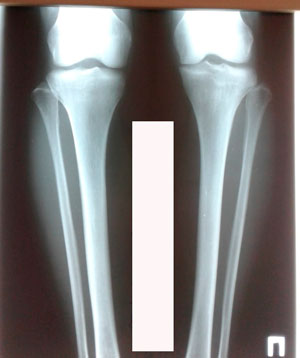

Исходник - 45 лет.

Дата операции - 24.03.2020

image-24-03-20-12-01.jpg

image-24-03-20-12-01-1.jpg

image-24-03-20-12-01-7.jpg